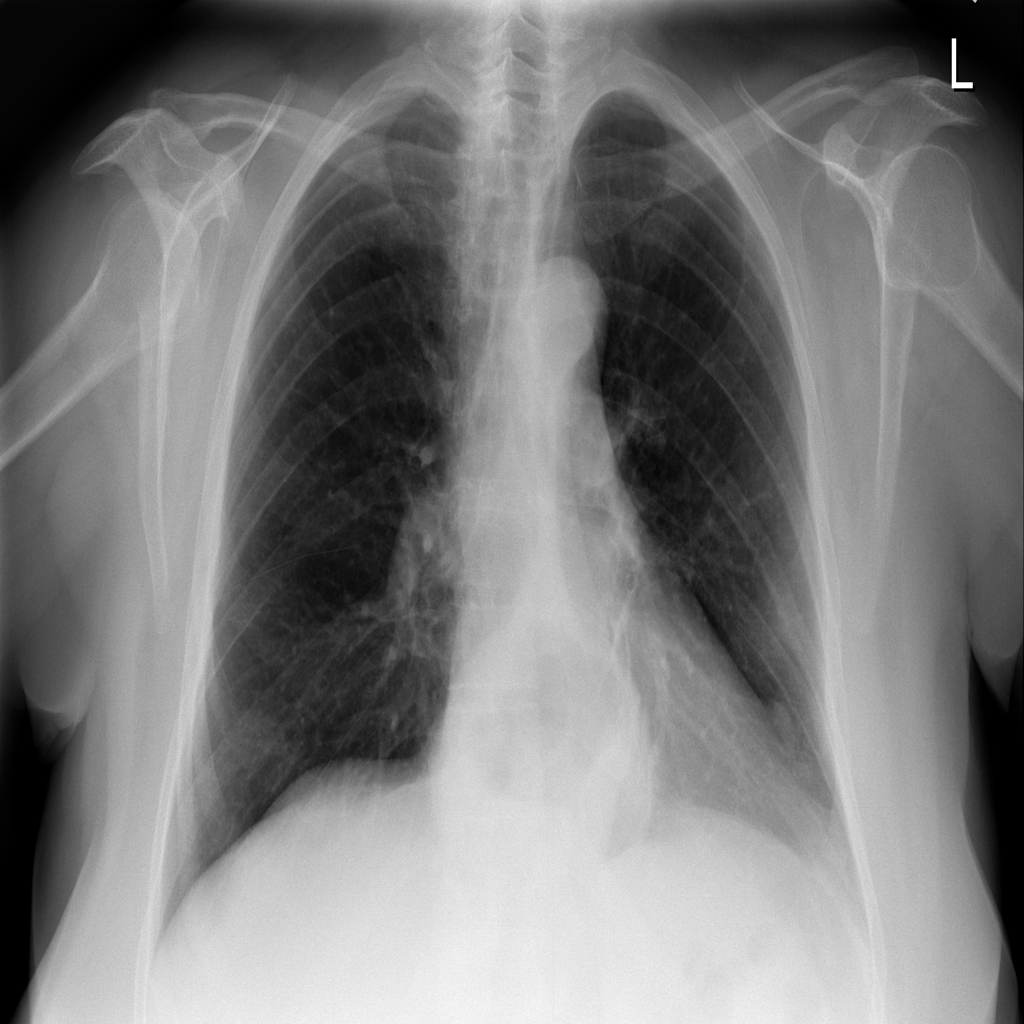

PAT-4F7E · IMG-000Hernia

PAT-4F7E · IMG-000

PA